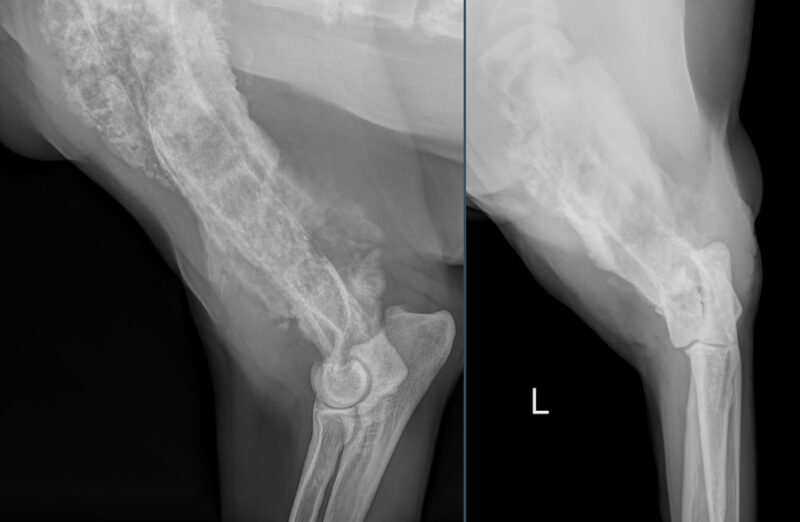

Vielen Dank für die Zusendung der Röntgenbilder. Ein wirklich eindrucksvoller Fall! Es liegen zwei Röntgenaufnahmen des linken Humerus, inkl. Ellbogengelenk, im medio-lateralen, sowie kaudo-kranialem Strahlengang vor. Begleitend besteht eine Röntgenaufnahme des Thorax in dextro-sinistralem Strahlengang (Abb. 1, Abb. 2). Im Röntgenbild der linken Vordergliedmaße zeigt sich im Bereich der gesamten Diaphyse des Humerus, bis in die angrenzenden metaphysären Abschnitte reichend, eine hochgradige, unregelmäßige osteoproliferative Reaktion (blaue Pfeile Abb. 3). Diese periostale Reaktion weist eine heterogene Röntgendichte auf. An ihrer ausgeprägtesten Stelle übersteigt die Proliferation den Durchmesser des normalen Humerus deutlich. Besonders an der kaudalen Humeruskontur besteht hochgradige, laminar geschichtete Knochenneubildung (gelbe Pfeile, Bild links).

Die Markhöhle (Medulla) erscheint hochgradig heterogen (blaue Pfeilköpfe). Entlang des Endosteums sind multifokale Irregularitäten (grüne Pfeilköpfe), sowie multifokale kortikale Lysen (rote Pfeile) sichtbar, die den Befund einer destruktiv-proliferativen Knochenerkrankung verdeutlicht. Eine pathologische Fraktur ist in den vorliegenden Aufnahmen nicht erkennbar.

Das umgebende Weichteilgewebe zeigt eine deutliche Umfangsvermehrung (hellgelbe Pfeile und Pfeilköpfe, Bild rechts). Zudem findet sich am proximalen Radius eine geringgradige, glattrandige periostale Reaktion (gelbe Pfeilköpfe, Bild links).